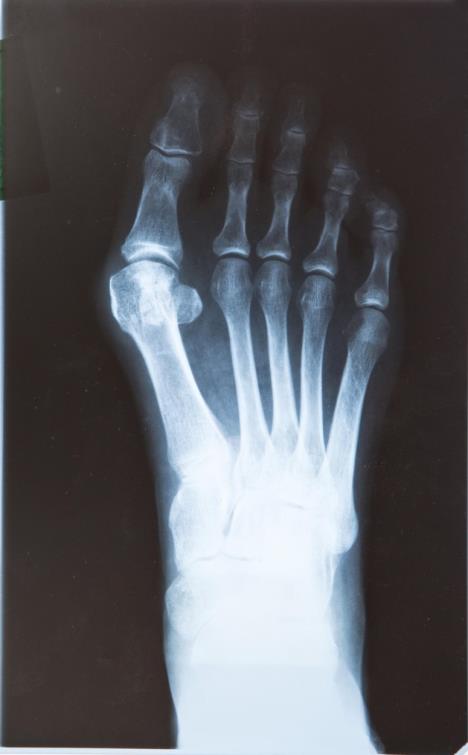

ČUKLJEVI MOGU DA PROĐU BEZ OPERACIJE! Sve što vam treba je OVAJ ČAJ za koji lekari ne govore!

Foto: Profimedia